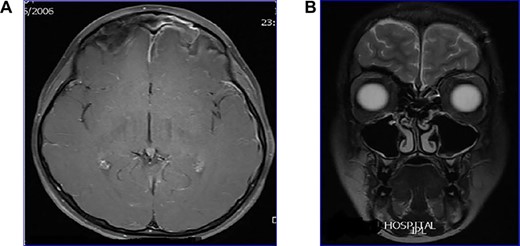

Young girl with 2-week history of unresolving sinusitis presented with fever, headache, vomiting and drowsiness diagnosed as a case of bacterial meningitis as a complication of frontal sinusitis. MRI (Fig. 2A) showed a left frontal sinusitis, meningitis and sagittal sinus thrombosis. Patient underwent endoscopic drainage of the sinuses with a combination of intravenous antibiotics. Patient had an excellent recovery with no complications, as shown in post-treatment MRI (Fig. 2B).

(A) MRI showing frontal sinusitis with meningitis and sagittal sinus thrombosis, (B) post-treatment MRI with clean sinuses and brain.